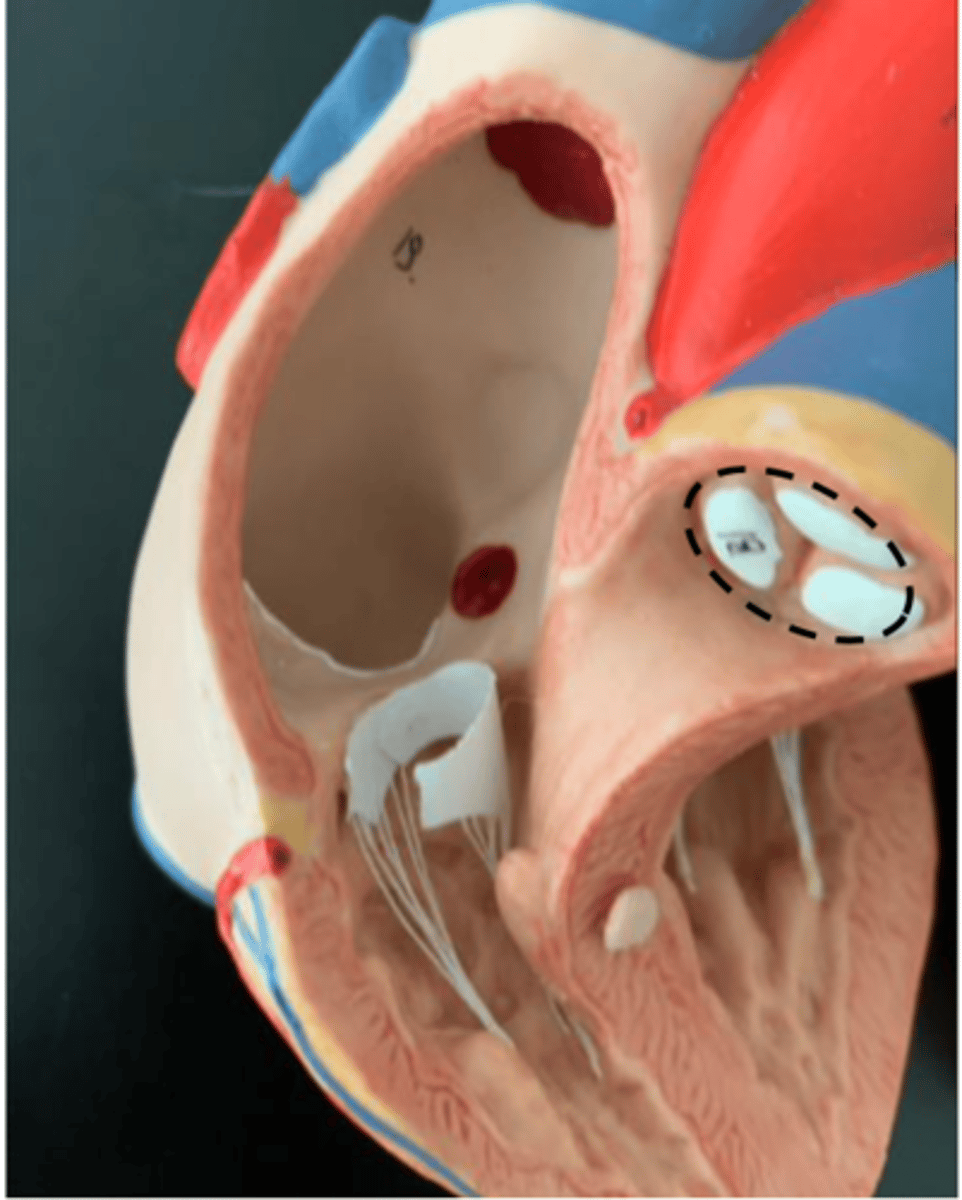

pulmonary semilunar valve

valve inside the pulmonary trunk (no strings attached)

<p>valve inside the pulmonary trunk (no strings attached)</p>

aortic semilunar valve

valve inside the ascending aorta (no strings attached)

<p>valve inside the ascending aorta (no strings attached)</p>